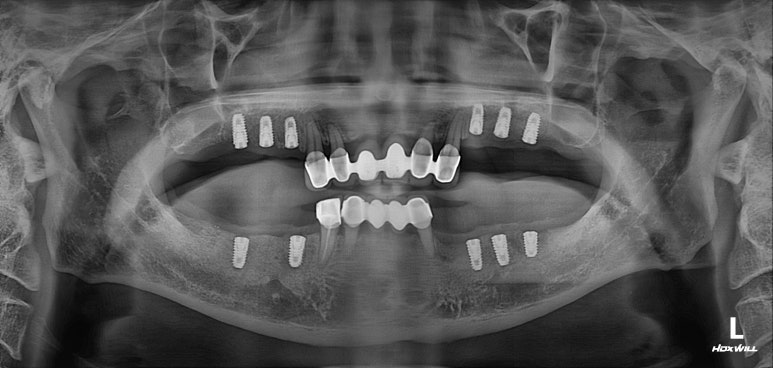

모든 최종 보철물을 연결하고 나서 치과용 파노라마 사진입니다.

정말 깔끔하게 제작된 것을 보시 수 있을겁니다.

'미적 기준'은 보편적인 측면이 있습니다. 뭔가 나란하고 비율이 대칭인 임플란트는, 잘 모르는 사람이 봐도 잘 되었구나~~ 라고 생각하게 만들어주죠 ^^

제가 가진 수술 경험을 비롯한 노하우와, 오스템 임플란트의 네비게이션 임플란트 시스템이 합작해낸 결과물!